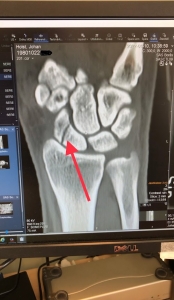

Jag tänkte jag skulle ge en liten uppdatering nu efter helgens EC-tävling i Österrike. Som ni säkert har sett på mina sociala medier så jag skadat min vänstra handled. Det hände dagen efter vi landade, så skulle vi åka några träningsåk och då fick jag ett felskär och ramlade lite olyckligt och landade på handen […]

Jag var hos ortopeden igår och skulle kolla min hand då jag har haft gips i tolv veckor nu. Senaste besöket så fick jag ju beskedet att det hade läkt långsamt men de trodde att det skulle vara bättre till den här gången. När jag hade varit på magnetkamera röntgen och kom tillbaka till läkaren […]

Då var man hos läkaren igår och fick lite mer information om hur det ser ut med min hand. Ja det var ju inte så kul om man säger så, kan ju börja med att jag träffade en handkirurg så han vet vad han pratar om. Det började med att han frågade om vad som […]